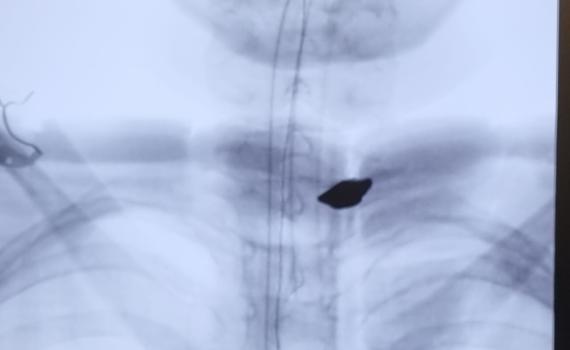

במהלך הניתוח הוצא מגופו של הילד רסיס באורך 18 מ"מ.

ד"ר נמרוד רחמימוב, מנהל המחלקה לאורתופדיה ב' וניתוחי עמוד שדרה, מסר בתום הניתוח המוצלח: "הרסיס הגדול ננעץ בחלק האחורי של החולייה ושבר אותה, אולם בדרך נס לא פגע בחוט השדרה עצמו. היה כאן מזל גדול".